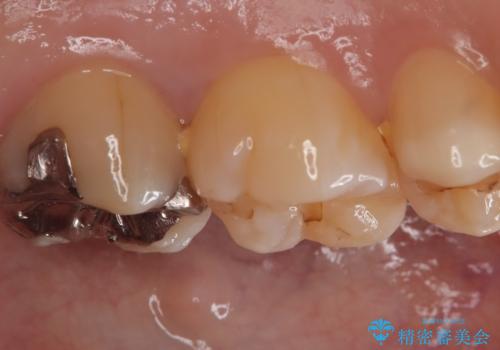

- 主訴:左上の銀の詰め物、笑うと見えそうで気になるので白くしたい。

保険適応のメタルインレーが入っていたため、適合性・審美性の良いセラミックインレーでのやり替えとなりました。

保険適用のメタルインレーを除去したところ、歯質との境目部分にカリエスを認めたため、カリエス除去しCR裏層の後、セラミックインレーを形成しました。